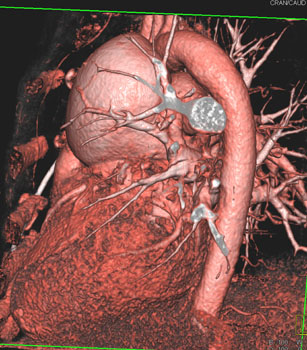

![]() | Question 12: 59 year old male with recent onset of chest pain as well as shortness of breath. The patient had a history of “some type of corrective cardiac surgery” as a child. What is the diagnosis? |